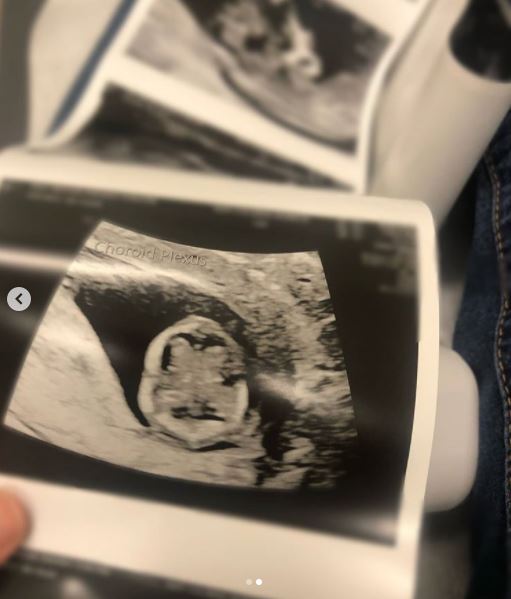

Pro-life activist shares remarkable scan of 12-week-old preborn baby’s brain

Pro-life activist Albany Rose recently shared a detailed ultrasound image of a friend’s 12-week-old preborn child. The image clearly shows the two hemispheres of the brain from the top — an ultrasound scan few will ever see.

“First and foremost, this baby is healthy and mama is so relieved there aren’t words,” said Rose. “This is a scan of the brain at 12 weeks. It just blew my mind! Because this is high risk, the scans were specific for the brain. You don’t generally get this on a standard [ultrasound].” According to the Endowment for Human Development, the corpus callosum of the preborn child — connecting the left and right hemispheres of the brain — forms between 11 and 12 weeks.